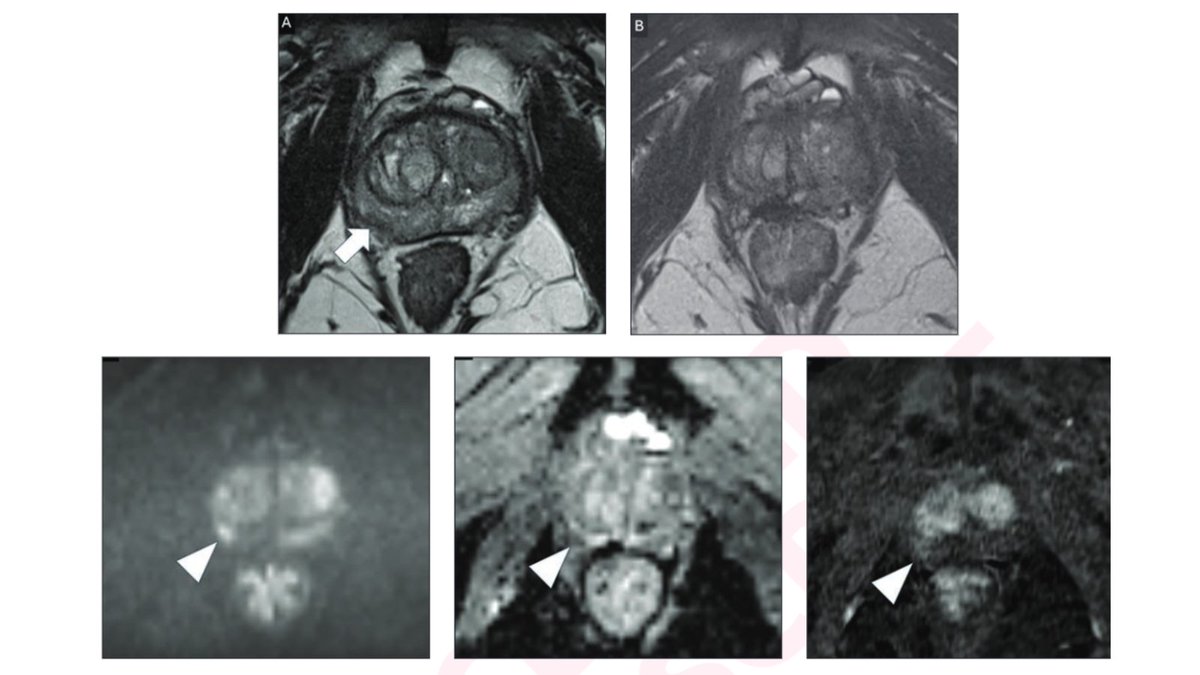

A technique that delivers high-intensity focused ultrasound to targeted tissue under #MRI guidance effectively treats intermediate-risk prostate cancer with minimal side effects, according to a study published in Radiology: bit.ly/3aGWUvp

MRgFUS-for-prostate-cancer Just out: early results of our phase II study for localized intermediate risk PCa rsna.org/news/2021/febr…

#5 Review Article: Magnetic resonance imaging-guided ultrasound ablation for #prostatecancer – A contemporary review of performance 👨‍⚕️👩‍⚕️ Mostafa Alabousi and Sangeet Ghai Read here 👉 fro.ntiers.in/B9oH Sangeet Ghai Mostafa Alabousi #MRI #Imaging